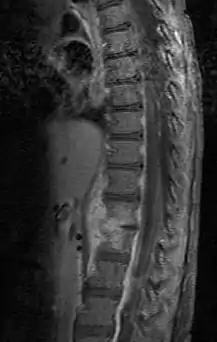

Diagnosis is usually apparent on MRI although plain X-rays and CT examinations can be suggestive. The MRI will reveal air changes in the disc and possibly even external involvement involving the bone or epidural regions. A biopsy may be performed and helps with diagnosis in some cases but often an organism is not obtained. C-reactive protein levels and ESR levels will be elevated and are useful for treatment. Often, the white blood cell count will be normal and the patient will be afebrile.

Discitis with anterior abscess (and disc space abscesses)